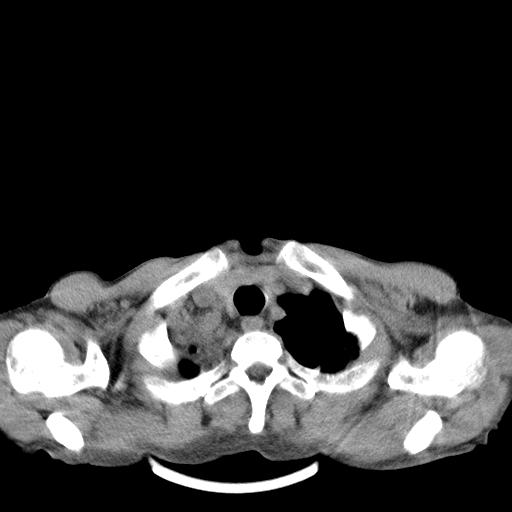

男性 75  咳嗽 一周前发热最高达39

右肺继发型tb并右侧tb性胸腔炎,右侧胸腔大量积液并右下肺膨胀不全,慢支肺气肿、多发肺大泡。建议抽胸水实验室检查并复查排除恶性在占位。

右上肺继发型肺结核,右胸腔中等量积液。

左上肺大泡。

结核的基础上有纵隔淋巴结肿大,右侧有胸水,但右侧纵隔反而窄,说明有肺有不张。

再就是右下肺有块影,和不张混合,还是不能除外肺癌。

补充材料,患者2月份ct片大致正常,双侧胸腔积液,2月份抽胸水未发现ca细胞,现患者发热,痰多,各气管通畅,